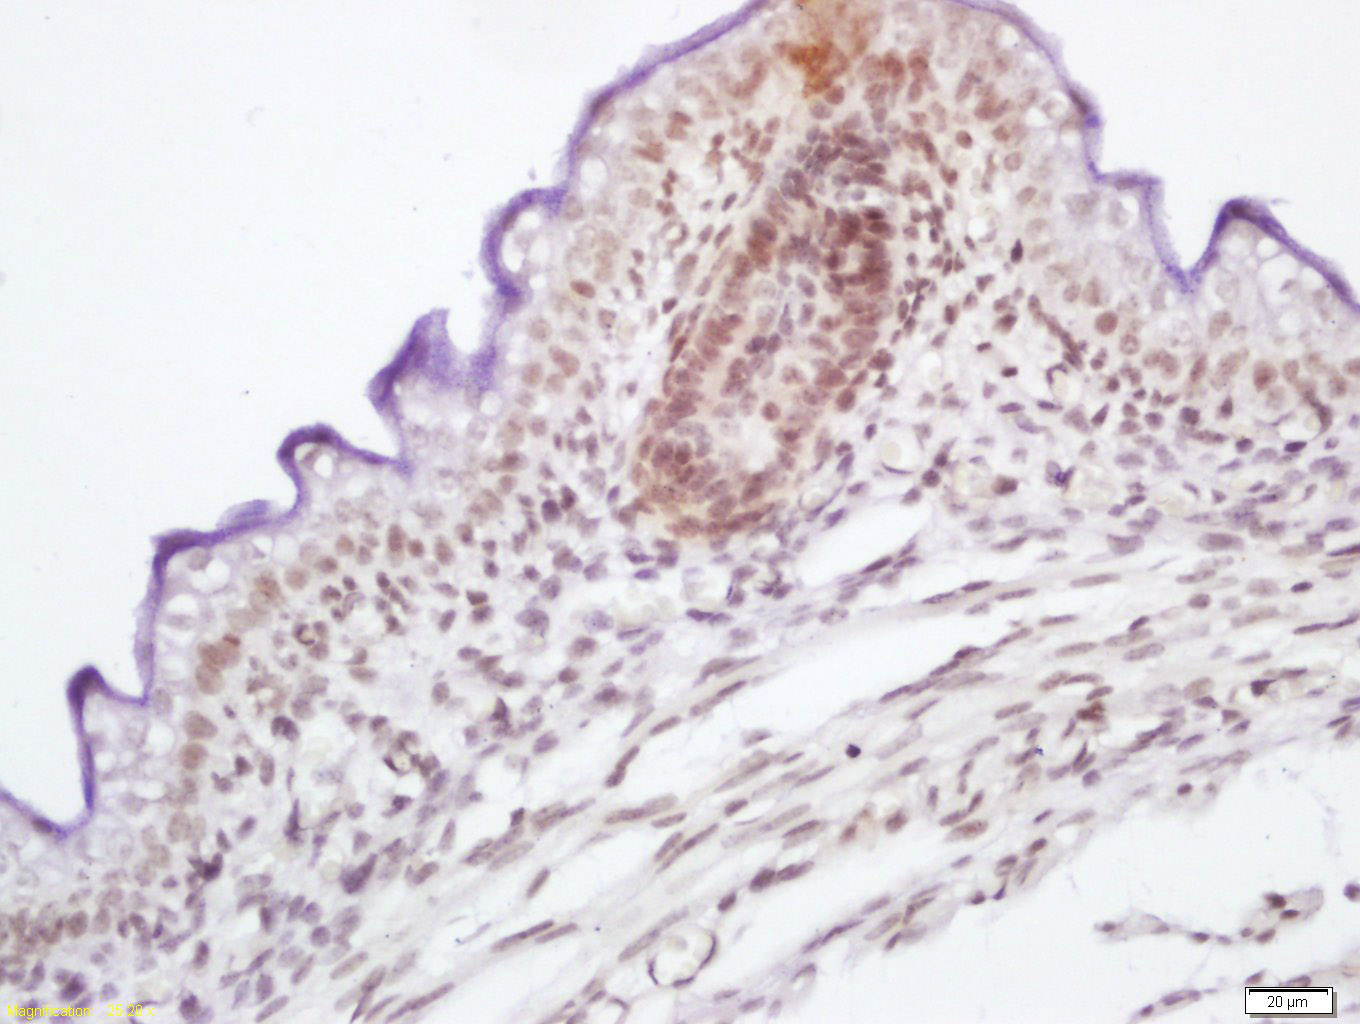

Tissue/cell: mouse embryo tissue; 4% Paraformaldehyde-fixed and paraffin-embedded; Antigen retrieval: citrate buffer ( 0.01M, pH 6.0 ), Boiling bathing for 15min; Block endogenous peroxidase by 3% Hydrogen peroxide for 30min; Blocking buffer (normal goat serum,C-0005) at 37℃ for 20 min; Incubation: Anti-phospho-c-Raf(Ser339) Polyclonal Antibody, Unconjugated(bs-5652R) 1:200, overnight at 4°C, followed by conjugation to the secondary antibody(SP-0023) and DAB(C-0010) staining